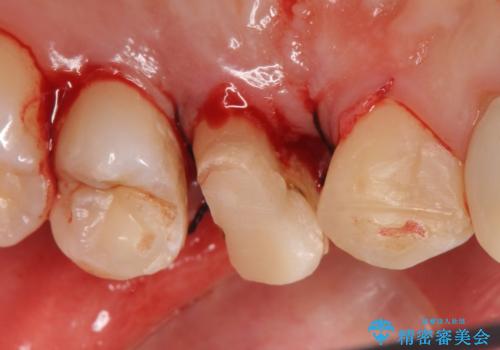

- 左上3、4番の見た目が気になるためセラミックにしたいといらっしゃった方の症例です。

左上4の補綴物を除去したところ縁下歯質だったため、歯牙の挺出を提案し行いました。

挺出終了後は歯肉切除および骨外科により歯周組織を整え、オールセラミッククラウンによる補綴を行いました。